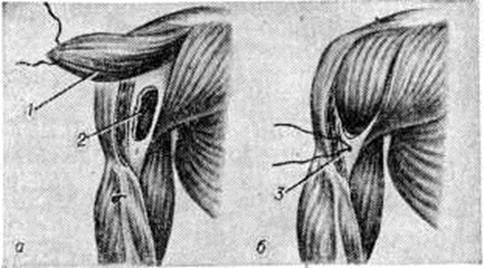

Воспаление начинается в мягких тканях краёв раны в виде диффузной воспалительной инфильтрации, вслед за которой на границе с зоной омертвения формируется демаркационная линия. Одновременно образуется экссудат, поступающий в полость раны и пропитывающий некротизированные ткани, подвергающиеся при этом расплавлению, а часто и гнилостному распаду. К 4— 5-му дню в зоне демаркационной линии образуются грануляции, обильно продуцирующие гной. К этому сроку проявляется и гнойное воспаление в отломках кости, которое протекает на границе с некротизированными тканями, сохраняя характер демаркационного. С началом нагноения омертвению могут подвергнуться связанные с периостом костные осколки и мягкие ткани, испытавшие коммоцию — зона резерва некроза по И. В. Давыдовскому. Очаг нагноения постепенно изолируется валом из грануляций, а в последующем и соединительнотканной капсулой. В нем располагаются свободные костные осколки, не удалённые при хирургической обработке раны, осколки, сохранившие связь с периостом, концы отломков, лишённые периоста, инородные тела, обрывки мягких тканей, распадающиеся кровяные свёртки (рисунок 3). Нагноение нередко распространяется в глубь мягких тканей и в толщу кости вдоль трещин и каналов, проделанных сместившимися в момент ранения костными осколками, что придаёт очагу сложные очертания (цветной рисунок 1).

В ходе нагноения происходит расплавление омертвевших тканей под действием ферментов гноя и выделение их из раны, а также секвестрация омертвевших участков кости, находящихся в очаге нагноения. Темпы секвестрации снижаются при обширном параоссальном нагноении, задержке гноя в ране, тяжёлой интоксикации.

В ходе нагноения в окружающих очаг тканях развёртываются пролиферативные и дистрофические процессы. В результате пролиферации тканей возникает гноеродная оболочка, а затем формируется костная мозоль (смотри полный свод знаний) с последующей консолидацией перелома или образуются лишь костные разрастания по краям отломков (рисунок 4). Возникшая костная мозоль включает в себя гнойники с секвестрами (цветной рисунок 2) и играет т. о. роль секвестральной капсулы, из которой свищевые ходы ведут на поверхность кожи (рисунок 5). Дистрофические изменения выражаются в диффузной рарефикации, а позже в очаговой эбурнеации кости (смотри полный свод знаний) в зоне образования мозоли. В окружающих мягких тканях и в соседних суставах развиваются явления атрофии.

Оперативное лечение состоит в декомпрессивной остеоперфорации в 2—3 участках кости на протяжении с целью вскрытия и дренирования костномозгового канала, устранения повышенного внутрикостного давления, улучшения кровоснабжения кости, предотвращения дальнейшего её некроза, улучшения состояния больного и прекращения у него болей.

Остеоперфорация у детей производится под общим обезболиванием. После обнажения поражённого участка кости через её кортикальный слой проникают в костномозговой канал с помощью электродрели или трёхгранного шила; в образованные отверстия вставляют катетеры для дренирования и промывания костномозгового канала. Иногда целесообразнее сначала ввести в кость иглу Кассирского чрескожно в области одного из метафизов с диагностической целью; при выделении из иглы под давлением крови с капельками жира или гноя, что подтверждает диагноз Остеомиелит, другой иглой Кассирского пунктируют второй метафиз и через эти иглы осуществляют промывание костномозгового канала. Ю. Ф. Исаков предложил перед промыванием вводить 0,25% раствор новокаина с целью деблокирования остеорецепторов, предотвращения нейротрофического остеопороза, уменьшения воспалительной реакции и ускорения восстановления местных обменных процессов, а затем через одну из игл одномоментно вводить шприцем около 1 л изотонического раствора хлорида натрия с антибиотиками. В последующие 5—7 дней внутрикостные промывания повторяют 2 раза в день тем же количеством раствора, но проводят его капельно (90 капель в 1 мин). В состав вводимого раствора могут входить протеолитические ферменты. Подменять декомпрессивную остеоперфорацию широким вскрытием костномозгового канала с удалением продольного фрагмента кости (путём трепанации) недопустимо, так как это ведёт к значительному ухудшению состояния больного, способствует диссеминации гнойного процесса и повышает риск летального исхода.

Лечение эпифизарного Остеомиелит проводят повторными пункциями сустава с отсасыванием выпота или гноя и введением в полость сустава антибиотиков. Разрез мягких тканей показан только при образовании параартикулярной флегмоны, которая возникает при прорыве суставной капсулы. При явлениях гнойного артрита и неэффективности повторных пункций сустава производят артротомию (смотри полный свод знаний) в точке наибольшей флюктуации. Длина разреза суставной капсулы у грудного ребёнка не должна превышать 1—2 сантиметров.